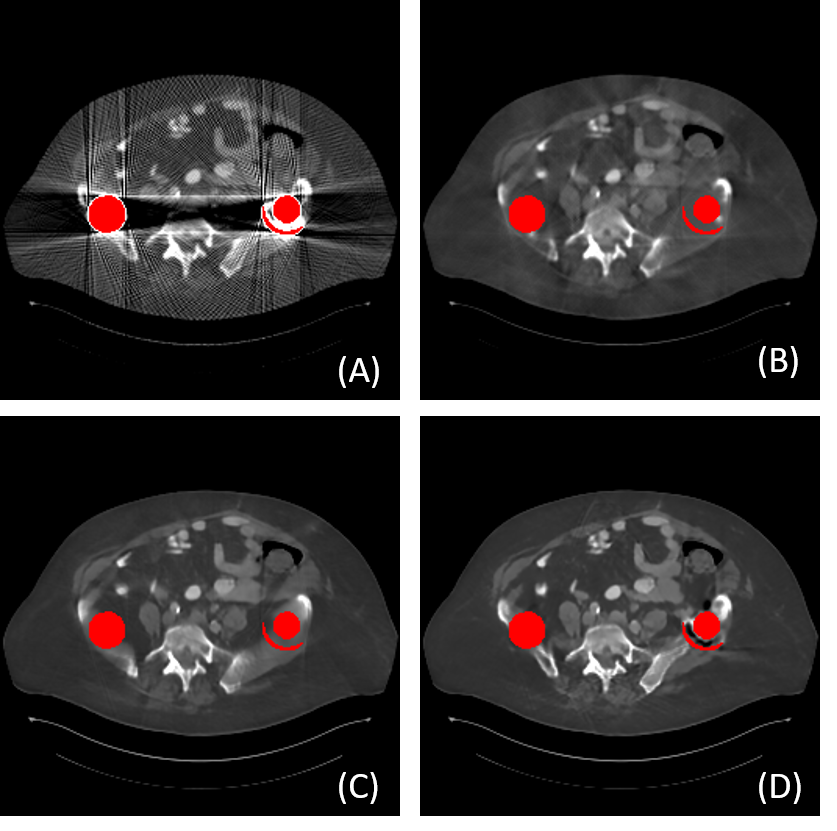

To tackle these problems mentioned above, in this paper, we propose a novel Interactive Dual-dOmain paraLlel network for CT MAR, dubbed as IDOL-Net. The proposed IDOL-Net is composed of two modules as depicted in Fig. 1. The disentanglement module introduces the idea of disentanglement representation to generate high-quality prior sinogram and image as the complementary inputs. The follow-up refinement module consists of two parallel and interactive branches that simultaneously operate on image and sinogram domain, attempting to fully exploit the latent information interaction between both domains. The intermediate results exported from both branches are fused to exchange the useful features from each other. Finally, the image quality is further enhanced by the refinement module. A representative slice processed using different MAR methods is given in Fig. 1.

2) Qualitative comparisons: Fig. 6 shows the representative results of different methods on simulated data with different metal sizes. For better visualization, the metal masks are painted in red. Due to the fact that LI and NMAR are interpolation-based methods directly discarding the projection data in metal trace, the metal information is lost and the corrected sinogram cannot keep the continuity at the boundaries of metal trace, leading to blurred tissues around the metals and remarkable secondary artifacts. Although CNNMAR fuses the results of different MAR methods, the improvement is quite limited. ADN achieves better performance on structure recovery around the metal implants than LI, NMAR and CNNMAR, and even DuDoNet in some cases, but it also can be noticed that in the second case (Fig. 6 (F2)), the shadow artifacts are not well suppressed and the details covered by the artifacts are hard to identify. This phenomenon probably lies in that ADN is essentially a post-processing method, which does not leverage the sinogram information. Compared to other methods, DuDoNet and the proposed IDOL-Net have the best performance on artifact reduction, but DuDoNet cannot recover the structures and tissues around the metal well, which can be clearly observed in the magnified yellow boxes in Fig. 6 (G2) and (G3). Our proposed IDOL-Net not only effectively removes most artifacts but also recovers the details better than all the other methods in all cases.

5.4 Experimental results on clinical data

To evaluate the robustness of our IDOL-Net for clinical practice, clinical CT images were tested and Fig. 7 shows the visual comparisons of one representative slice processed using different methods. The metal was segmented by the threshold of 2000 HU and the metal mask is painted in red for better visualization. The test image was normalized to the same range as the training data and the results were obtained using the model trained with simulated dataset used in the previous subsection. In Fig. 7 (A), the metal leads to severe artifacts, which covers some tissues, especially near the metal. It is observed that LI, NMAR and DuDoNet cannot retrieve the tissues around the metal, but due to the utilization of dual-domain information, DuDoNet outperforms most methods in artifact reduction. Since the shadow artifacts around the metal is very heavy, ADN cannot do much about this, which is similar to the situation in simulated dataset. It is observed that IDOL-Net suppresses most of the metal artifacts and effectively preserves the anatomical structures around the metals, which demonstrates its potential for real clinical application.